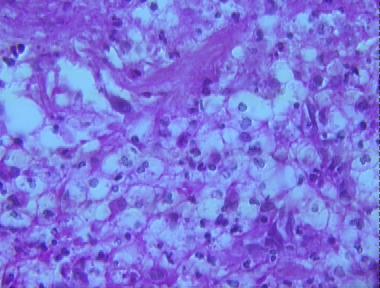

cryptococcosis

Histologic Features